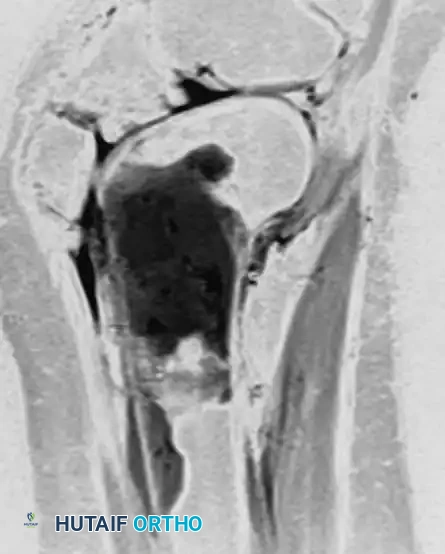

Anteroposterior and lateral radiographs of the right knee in a 51-year-old woman. The osseous structures appear relatively normal, belying the underlying pathology.

Coronal and sagittal MRI sequences of the same 51-year-old woman. The MRI reveals a massive, marrow-replacing lesion in the distal femur. Incisional biopsy confirmed a B-cell lymphoma. This highlights the critical rule: Lymphoma must be in the differential diagnosis for patients with severe bone pain and normal radiographs but abnormal MRI or bone scans.